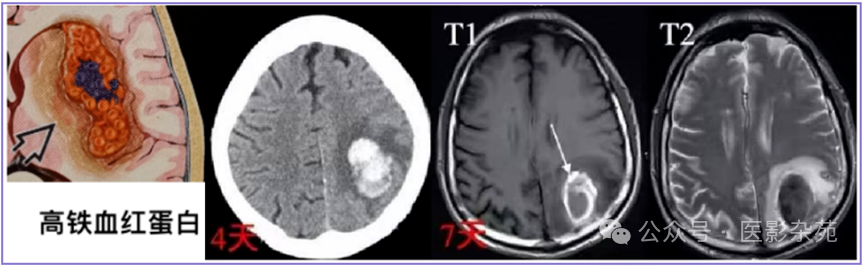

细胞内高铁血红蛋白

T1:信号逐渐增加(T1缩短)至高信号

T2:保持低信号

DWI:低

ADC:低